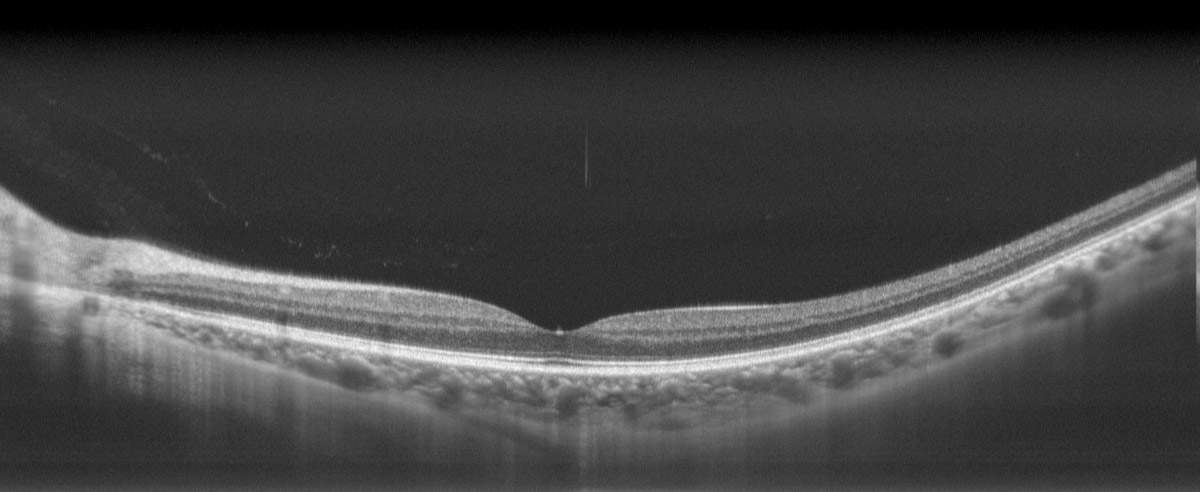

Ultra-Strong Tissue Penetration

Exceptional tomographic performance allows deeper fundus penetration, providing clear visualisation of choroidal and scleral tissue structures.